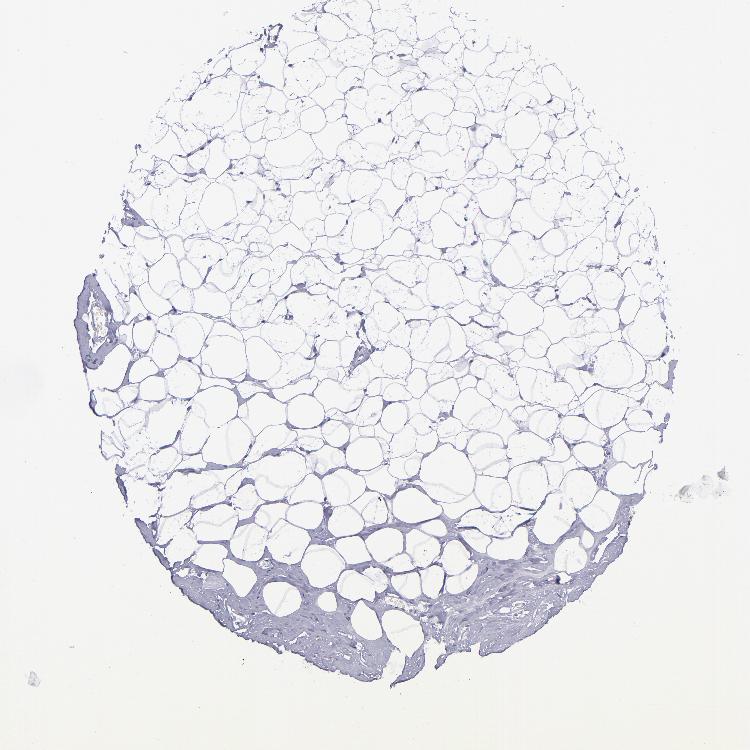

BREAST - Antibody stainingi

Antibody staining in the annotated cell types in the current human tissue is reported as not detected, low, medium, or high, based on conventional immunohistochemistry profiling in selected tissues. This score is based on the combination of the staining intensity and fraction of stained cells.

Each image is clickable and will lead to virtual microscopy that enables deeper exploration of all samples and also displays staining intensity scores, fraction scores and subcellular localization as well as patient and tissue information for each sample.

Antibody HPA007863Antibody CAB002226

Adipocytes Not detectedNot detected

Glandular cells LowNot detected

Myoepithelial cells Not detectedNot detected